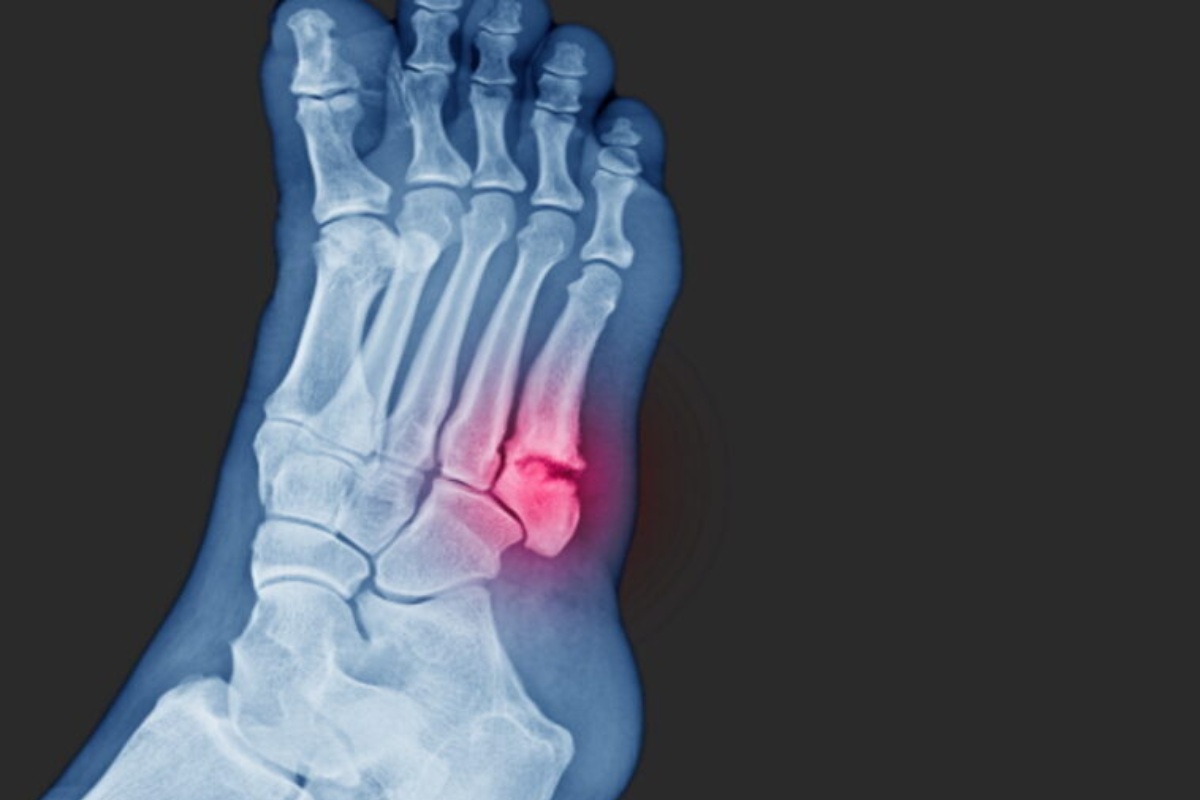

شکستگی جونز (Jones Fracture) یک شکستگی خاص در پایهی استخوان پنجم متاتارس پا است. این استخوان در بخش خارجی کف پا قرار دارد و شکستگی دقیقاً در نقطهای بین پایه و تنه اصلی استخوان اتفاق میافتد.

ویژگی اصلی که این شکستگی را از سایر شکستگیهای این استخوان متمایز میکند، محل آن است. این ناحیه به دلیل داشتن خونرسانی ضعیف، فرآیند بهبودی کندتری دارد. به همین دلیل، درمان آن ممکن است چالشبرانگیزتر باشد و گاهی خطر جوش نخوردن استخوان یا نیاز به درمانهای جدیتر وجود دارد.

پزشک ابتدا با پرسیدن سوالاتی در مورد چگونگی آسیب و زمان شروع درد، به ارزیابی اولیه میپردازد. سپس از طریق معاینه فیزیکی و فشار دادن آرام نواحی مختلف پا، محل دقیق درد را مشخص میکند. تشخیص قطعی معمولاً با تصویربرداری با اشعه ایکس (X-ray) انجام میشود. در مواردی که شکستگی در تصاویر اولیه مشخص نباشد، ممکن است از MRI یا سیتی اسکن استفاده شود.